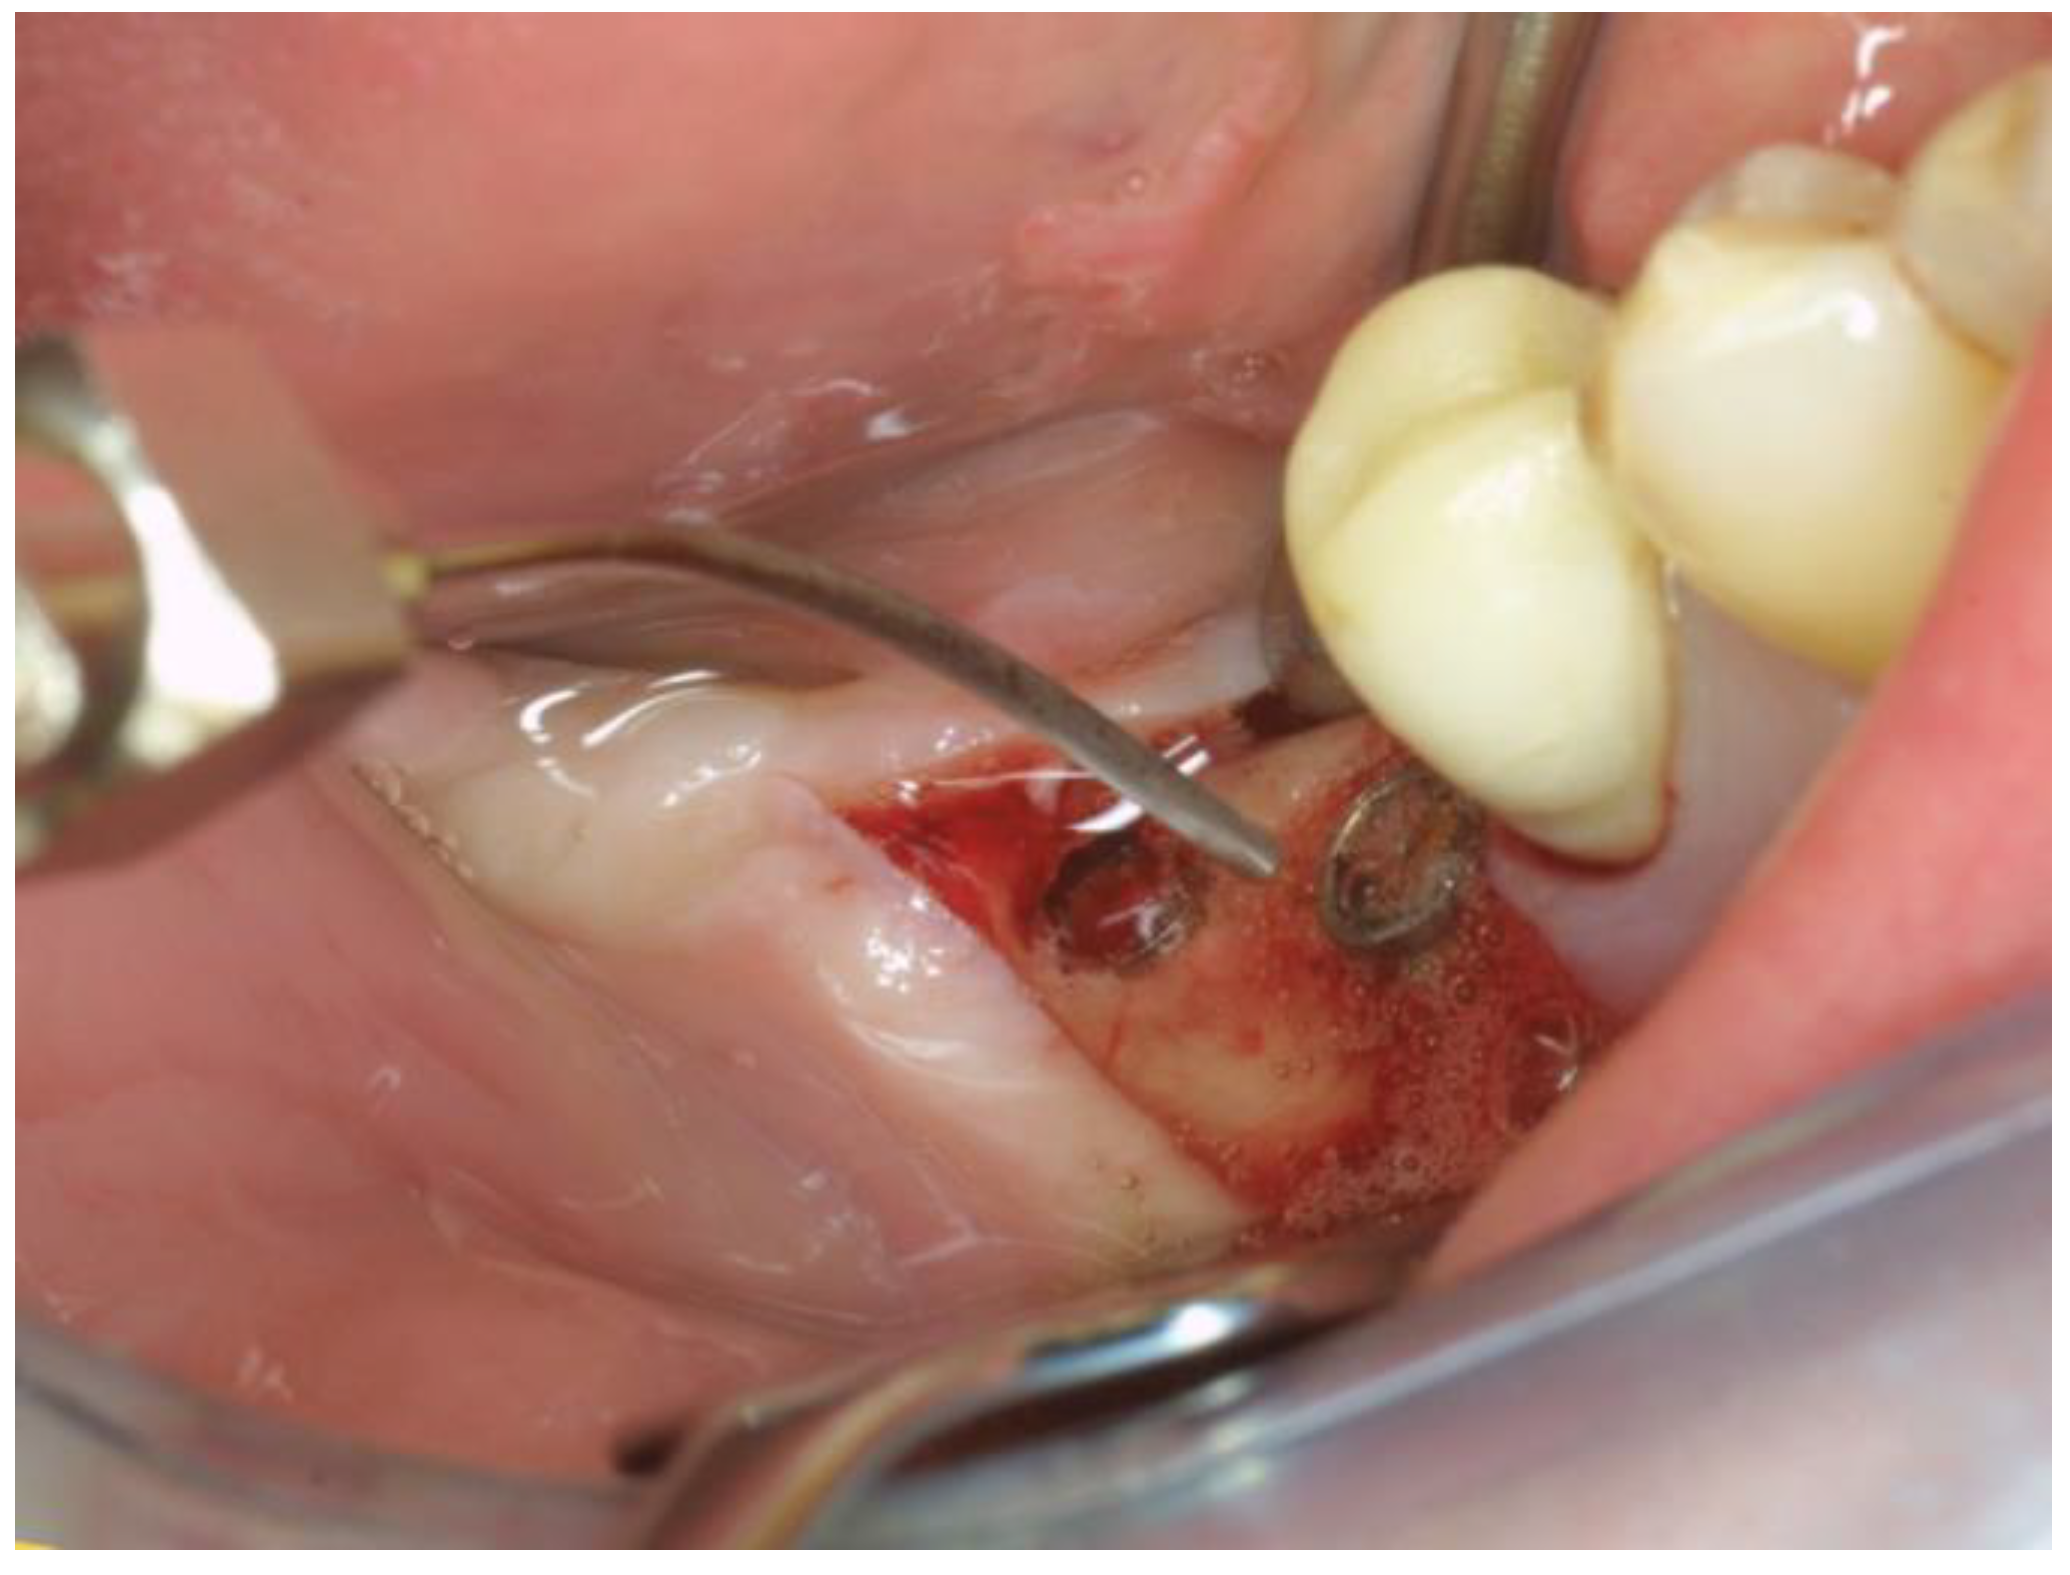

The OHLLT + Erbium:Yag surgical procedure consists of: local anesthesia; intrasulcular incision for a full thickness periodontal flap; Er:YAG laser (Pluser, Doctor Smile, Vicenza, Italy) first applied in order to remove granulation tissue (power: 1.8 W, frequency: 35 Hz, energy: 50 mJ, water: 20%, air: 60%); ultrasonic instrumentation for supra- and subgingival scaling combined with water–Betadine irrigation (5:1 ratio); air flow device with sodium bicarbonate powder (highly abrasive powder); subsequently, the OHLLT protocol was performed (Wiser diode laser, Sioxyl Solution, Doctor Smile, Vicenza, Italy): irrigation of peri-implant pockets with Sioxyl Solution; aspiration of Sioxyl Solution emerging from the gingival sulcus and leaving the remaining solution inside the pocket for 2 min; introduction of the HF Diode Laser Fiber 400 microns within the pocket and reaching the bottom, radiation of subgingival tissues with a back and forth movement using the dedicated program, 60 s per side (2.5 W peak power, high frequency, 10 KHz, power average 0.5 W, fluency 25,000 J/cm2, 416.66 J/cm2 per second). After the decontamination with OHLLT, the Er:YAG laser (Pluser, Doctor Smile) was used to treat implant surfaces (power: 0.8 W, frequency: 10 Hz, energy: 80 mJ, water: 60%, air: 60%) and then to create mechanical biostimulating effects on bone tissues (Figure 5) (power: 3.2–3.8–4.4 W, frequency: 20 Hz, energy: 160–190–220 mJ, depending on bone density, from lower to higher, water: 70%, air: 80%). Finally, a graft mix consisting of Bio-Oss granules, autologous bone chips, platelet-rich fibrin (PRF) and collagen membranes (45% Bio-Oss, 45% PRF, 10% autologous bone chips) was applied, finalizing with flap repositioning and suturing.

Figure 5.

Er:Yag (Pluser, Doctor Smile) in action on bone surfaces (power: 3.2–3.8–4.4 W, frequency: 20 Hz, energy: 160–190–220 mJ, depending on bone density, from lower to higher, water: 70%, air: 80%).